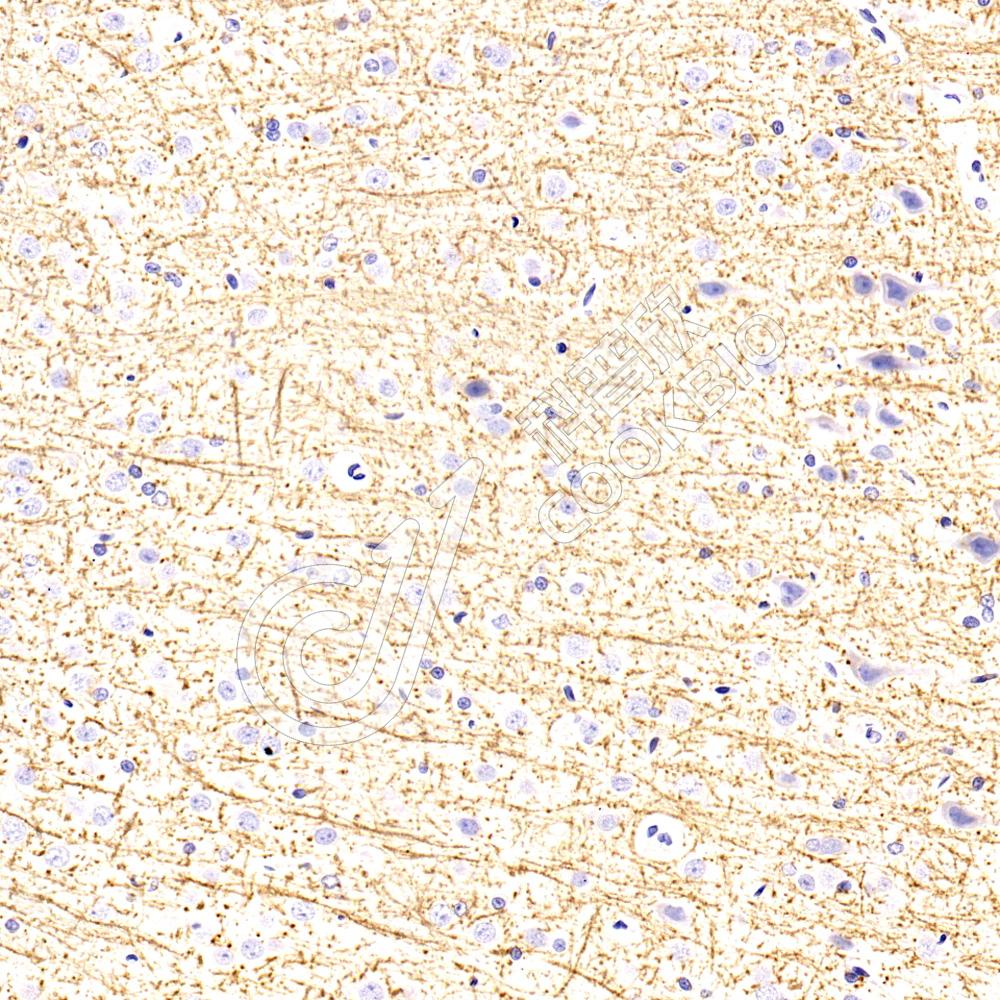

IHC检测FGF13蛋白(货号 K1339393).

样品: 小鼠脑, 4%多聚甲醛 (货号KSG1101) 固定12-24小时.

抗原修复: 柠檬酸抗原修复液(干粉, pH 6.0) (KSG1201), 98℃, 20分钟.

—抗: 1: 3000稀释, 4℃ 孵育过夜.

二抗: S-vision免疫组化多聚二抗(山羊抗兔),即用型 (货号KB3906), 室温孵育20分钟.

样品: 大鼠脑, 4%多聚甲醛 (货号KSG1101) 固定12-24小时.